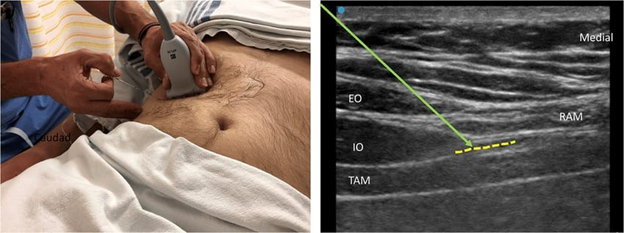

Trans abdominal plane block

TAB block<br />The tranversus abdominis plane (TAP) block has become one of the most common truncal blocks performed for postoperative analgesia after abdominal surgeries. <br />Regional anesthesia for abdominal wall procedures can be performed using a variety of peripheral nerve blocks. These blocks are typically ultrasound (US) guided and involves injecting a local anesthetic (LA) solution into interfascial planes. US-guided transversus abdominis plane (TAP) block implicates the injection of LA in between the transversus abdominis (TA) and internal oblique (IO) muscles. The TAP block can also be targeted using anatomical landmarks at the level of the Petit triangle. <br />Regional anesthesia for abdominal wall procedures can be performed using a variety of peripheral nerve blocks. These blocks are typically ultrasound (US) guided and involves injecting a local anesthetic (LA) solution into interfascial planes. US-guided transversus abdominis plane (TAP) block implicates the injection of LA in between the transversus abdominis (TA) and internal oblique (IO) muscles. The TAP block can also be targeted using anatomical landmarks at the level of the Petit triangle. <br /> <br />Bilateral TAP blocks are used for midline and transverse abdominal incisions, such as umbilical or ventral hernia repair, cesarean deliveries, hysterectomy, and prostatectomy. TAP blocks are part of multimodal pain management for abdominal surgeries, which adds analgesic benefit to the patients, reducing postoperative opioid requirements. <br />TAP block are usually placed intraoperatively, either before surgical incision or at the end of the procedure before emergence from anesthesia. The efficacy of the TAP block is dependent on the spread of LA across the interfacial plane. <br />The TAP anatomical compartment is a plane that is located between the internal oblique and transversus abdominis muscles and contains the T6–L1 thoracolumbar nerves .<br />The anterior cutaneous nerve from the T6–T11 segments gives rise to intercostal (IC) nerves, which supply sensitivity to the skin and muscles of the anterior abdominal wall. The T9–T11 IC and T12 subcostal (SC) nerves penetrate the transversus abdominis plane compartment posterior to the midaxillary line .<br /> <br />Indications<br />Provide analgesia after an abdominal wall procedure in a variety of abdominal surgeries are the indications of the TAP block. The TAP block can be performed for open abdominal surgeries as well as laparoscopic procedures. The TAP block is an easier and less risky substitute for epidural anesthesia in postoperative pain control for abdominal surgeries.<br />Contraindications<br />This procedure is contraindicated in the following scenarios:<br /><br />Patient refusal<br />Infection over the site of of injection<br />Allergy to local anesthetics <br />Caution should be maintained in patients that are on therapeutic anticoagulation, pregnant and, where anatomical landmarks are difficult to distinguish (like very thin patients, elderly, or deconditioned).<br /><br />Equipment<br />The following are the necessary materials to perform a TAP block .<br />Ultrasound machine with a linear transducer. (Sometimes a curvilinear transducer might be needed, if the patient is obese or if performing a posterior approach)<br />Sterile ultrasound probe cover sleeve<br />Sterile ultrasound gel<br />Sterile towels<br />Sterile gloves<br />Antiseptic for skin disinfection, such as chlorhexidine 2%<br />Nerve block needle (50-mm to 100-mm, 20-gauge to 21-gauge needle) with tubing<br />Two 20-mL syringes containing the local anesthetic solution<br />Local Anesthetic Agent: Ropivacaine, Bupivacaine or Liposomal Bupivacaine<br />One 5ml syringe containing lidocaine for skin local anesthesia (if the patient is awake)<br />Basic physiological monitors: EKG, pulse oximeter and blood pressure monitor<br />If performing the block in an awake patient: A 5-ml syringe with needle for skin infiltration with Lidocaine 1% local anesthetic<br />Complications<br />Complications related to TAP blocks are rare. Some complications have been reported including:<br /><br />Bowel perforation<br />Hematoma<br />Liver/Spleen laceration<br />Intrahepatic injection<br />Intraperitoneal injection of local anesthetic<br />Retroperitoneal hematoma due to vascular injury<br />Transient femoral nerve blockage<br />Local infection<br />Intravascular injection<br />Local Anesthetic systemic toxicity<br />TAP block provide analgesia for 12 hours at least , it can reach to 24 or 36 hours according to efficiency of the medicine has been used & professional hand that applicate it . <br /><br />By Dr. Amassi Yakdhan